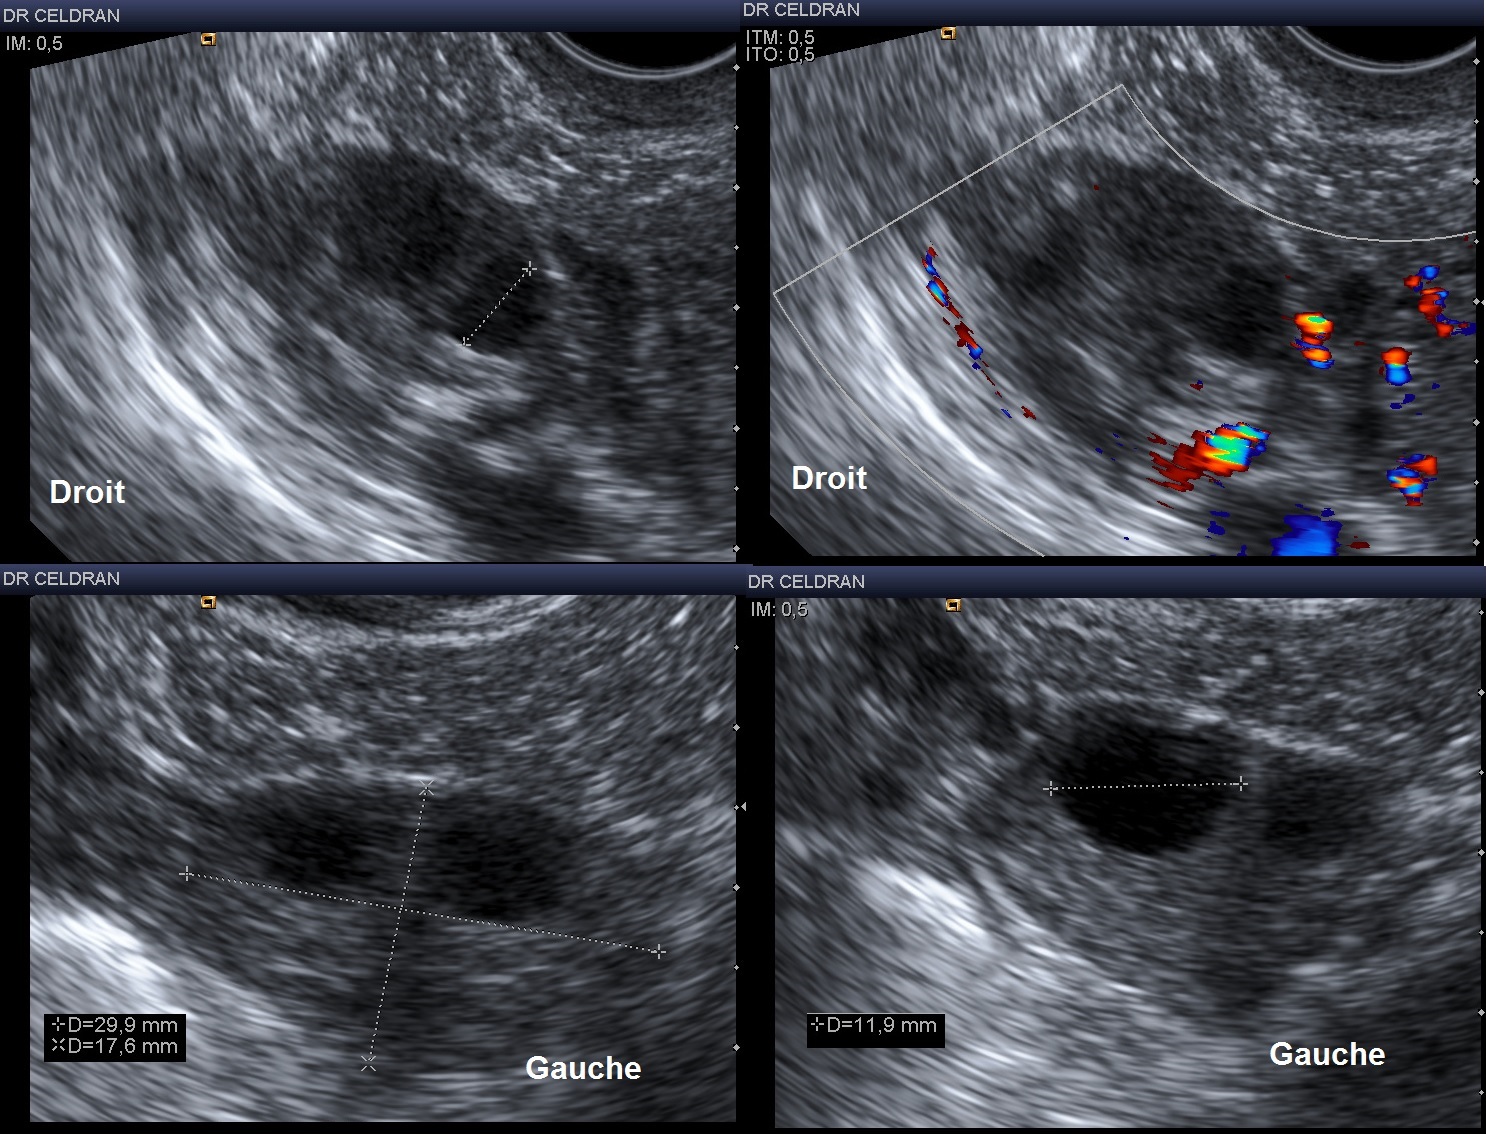

Ovaires normaux par voie endovaginale chez une patiente en période d’activité génitale.

- Hypoéchogènes ou isoéchogènes par rapport à l’utérus, les ovaires ne sont pas toujours repérables : ovaires petits, patiente obèse, gaz intestinaux, absence de follicules (ménopause)

- L’ovaire contient en général 5 à 7 follicules de moins de 10mm (aspect pluri-folliculaire physiologique)

- Le follicule dont la taille atteint plus de 14mm peut-être concidéré comme dominant : il commence à se dissocier échographiquement entre le 8ème et le 10 jour du cycle, pendant que les autres follicules vont subir une involution assez lente.

Dimensions de l'ovaire

Ecarts Moyens

Longueur (mm)

25 - 35

Largeur (mm)

12 - 25

Epaisseur (mm)

10 - 15

Surface (cm2) = L x l x 0.8

3 - 6

Volume (cm3) = L x l x Ep x 0.5

3 - 10